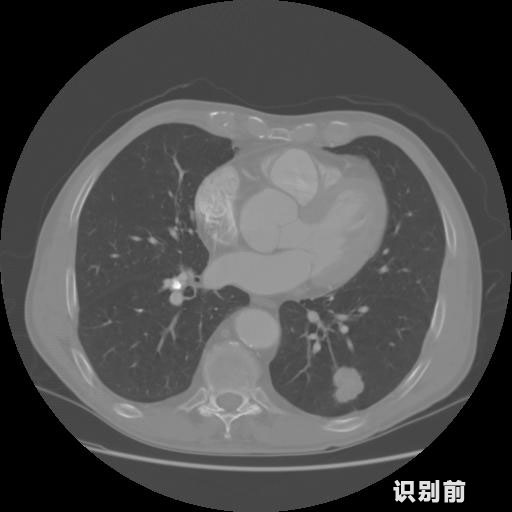

英特健康AI深度學習醫(yī)療圖像識別系統(tǒng)案例_胸部CT

1.發(fā)現(xiàn)肺結節(jié)的可能性為95.56%---位于框指數(shù)位置:[331.70554 366.13406 365.21707 403.96234]